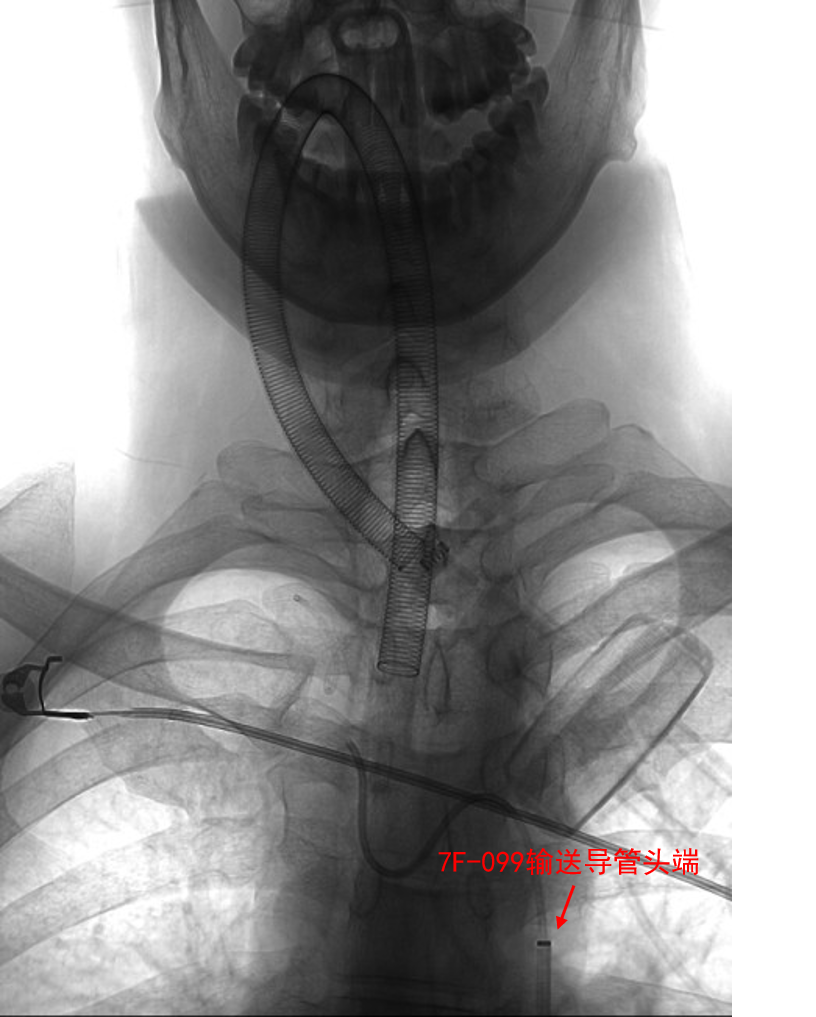

- 全麻,右侧股动脉穿刺,采用同轴技术,在泥鳅导丝+VTK导管辅助下将深瑞达7F 90cm输送导管置于右侧颈内动脉Cl段。

动脉长鞘怎么置入深谋远路 | 千人皆翘首,万唤今始来——国内首款7F长鞘在血流导向密网支架联合弹簧圈栓塞治疗动脉瘤的首次应用_https://www.jmylbn.com_新闻资讯_第24张

VTK加导丝将深瑞达7F输送导管输送至右侧ICA

- 5F 115cm颅内支持导管在泥鳅导丝支撑下超选入右侧颈内动脉C3段内。支架微导管先经5F颅内支持导管在微导丝支撑下超选入右侧大脑中动脉M1段。后微导管塑形后经深瑞达7F 90cm输送导管在微导丝支撑下超选入动脉瘤腔内。